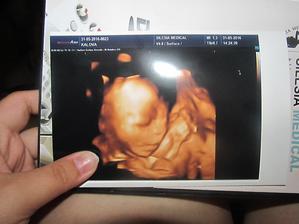

Klokan přiletí v září

jééé, krásný bobišek 😉 a už takový velký...